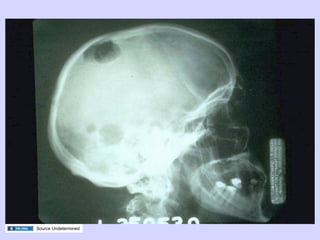

Multiple Myeloma

Source Undetermined